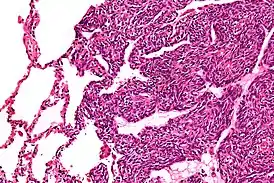

![]() Микрофотография из монофазной синовиальной саркомы | |

- Монофазная

- при монофазной саркоме — в основном плохой, редки случаи (единичны), когда больные выздоравливают полностью, часты метастазирующие стадии в лёгкие (до 60 % случаев).

Высокая степень рецидивов, происходящих при монофазной саркоме делает её крайне злокачественной опухолью[3].